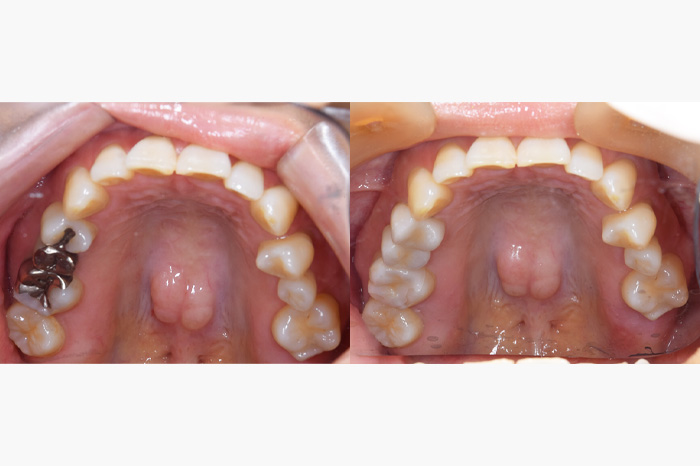

全顎のケース

銀歯を全部外してセラミックの詰め物、被せ物にしたケースになります。銀歯の中では虫歯になっている事が多く、よく私もそういうケースを目にします。こちらのケースでは、虫歯が大きくなっており、残せない歯があったため、インプラントを使用している部分もあります。

また、銀歯があると金属アレルギーを発症しやすくなったり、ひどくなると掌蹠膿疱症といって、手足がかゆくなったりすることもあります。金属アレルギーがある方は早めに金属の歯を外して、金属アレルギーと関係のない詰め物や被せ物を入れることをお勧めいたします。

| 年齢 | 50代・男性 |

|---|---|

| 主訴 | 銀歯をやりかえたい |

| 治療内容 | 左下の奥歯に歯がありませんでしたのでインプラントを行います。また気にされていた銀歯をすべてセラミックでやり直しました。 また、上の前歯に入っていた被せ物も一部歯にフィットしていない部分もありましたのであたらしく作成しました。 |

| 治療費 | ジルコニアボンドクラウン 11本: 合計1,815,000円(税込) (165,000円×11本) ジルコニアステインクラウン 6本: 合計660,000円(税込) (110,000円×6本) インプラント 1本: 合計539,000円(税込) セラミックインレー 5本: 合計275,000円(税込) (55,000円×5本) |

| 治療期間 | 6ヶ月 |

| リスク・副作用 | 全顎にわたる治療は噛み合わせが重要なため期間がかかります。 インレー、クラウンセット後にしみるといった症状がおこることが あります。 インレー、クラウンセット後に痛みがでて神経をとらないといけなく なることがあります。 |